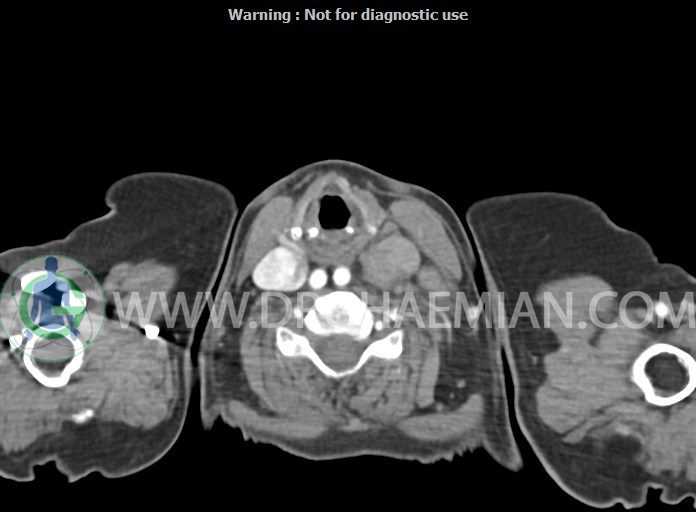

در سی تی اسکن اسپیرال از گردن با تزریق (مولتی دیدکتور 16 با مقاطع ظریف و بازسازی های ساژیتال و کرونال):

– تصویر توه های نسج نرمی oval shape متعدد با Enhancement تقریباً هوموژن، قرار گرفته در سمت چپ گردن، در لول غضروف کریکوئید با اثر فشاری شدید و compression ورید ژوگولار، با گسترش تحتانی به اینفراکلاویکولار چپ، به حداکثر ابعاد 28x50mm (با Enhancement مختصر هتروژن در این توده)

در درجه اول مطرح کننده لنفادنوپاتی متاستاتیک مطرح می باشد بالین، تومورهای منشأ گرفته از غلاف عصبی زنحیره سمپاتیک چپ گردنی، شبکه براکیال و لنفوم نیز در DDX قرار دارند. لذا نمونه برداری بافتی جهت بررسی بیشتر توصیه می شود.

– اسکولیوز مهره های سرویکال با تحدب به راست، احتمالاً در زمینه اثر فشاری توده های مذکور

مشهود است.